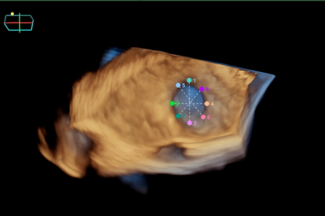

Coronary lithoplasty is a promising technique that can overcome issues regarding the treatment of undilatable, heavily calcified, de novo, and in-stent restenotic lesions, allowing plaque modification and successful stent deployment, as...

3D-OCT revealed extensive fracture and distortion of the struts in the distal portion of a stent, presumably caused by aggressive postdilation at the time of implantation. This was managed successfully with the insertion of a new coronary...